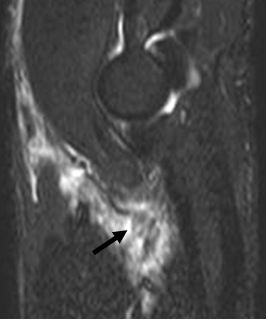

Fig 40 A. Ruptura retraída en tendón del biceps.

RM sagital en STIR. Ruptura retraída del tendón (Flecha), con cambios inflamatorios asociados.